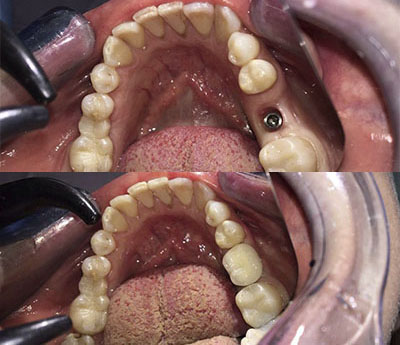

Implantul dentar este un dispozitiv confecționat din titan, care are rolul de a înlocui absența unuia sau mai multor dinți. Implantul îndeplinește funcția de radacină pentru viitoarea coroană dentară. Este fixat după intervențiile pregătitoare.